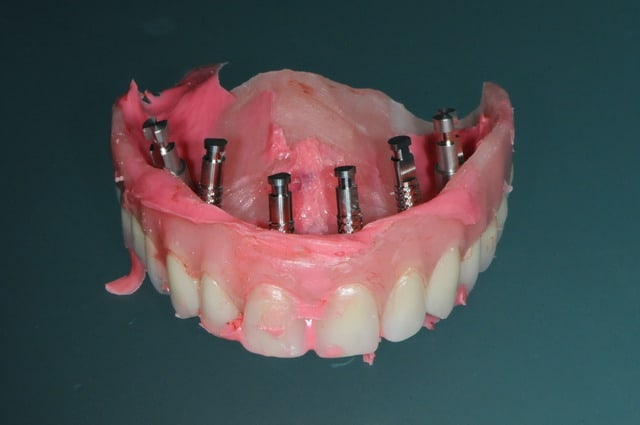

voici un cas en images, j'espère que ça plaira, ça fait un moment que je n'ai rien posté sur nonol et suis en manques de critiques et de compliments.

la patiente a été opérée hier et j'ai mis ses prothèses aujourd'hui.

la veille de l'intervention j'ai imprimé le model 3 D.